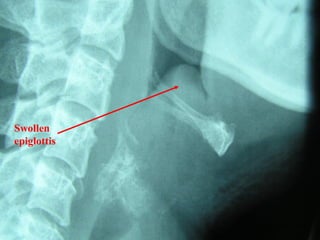

Epiglottitis

Indirect Laryngoscopy

Flexible Fiberoptic nasopharyngoscope

Lateral neck X-ray - thumb sign

Normal

epiglottis

Swollen